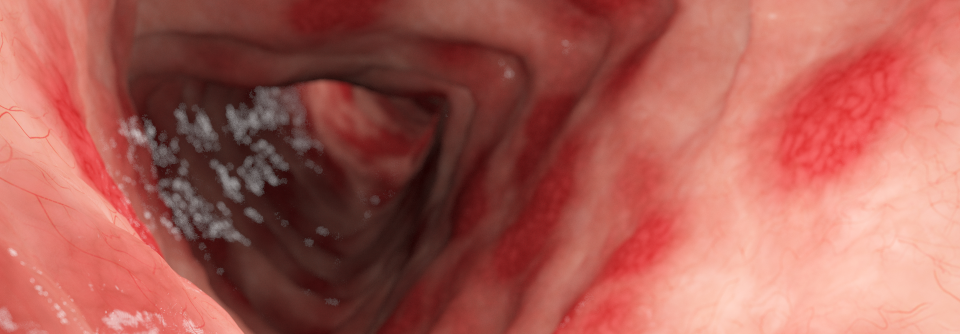

Anzeichen der Colitis Ulcerosa finden sich nicht nur im Darm (links). Die Patienten können gelegentlich Geschwüre an Zunge, Lippen, Gaumen oder Rachen aufweisen (rechts). Anzeichen der Colitis Ulcerosa finden sich nicht nur im Darm (links). Die Patienten können gelegentlich Geschwüre an Zunge, Lippen, Gaumen oder Rachen aufweisen (rechts). © fotolia/crevis; wikimedia/TheBlunderbuss

Während der Erstdiagnose und falls spezifische Symptome auftreten, soll eine komplette körperliche Untersuchung erfolgen – einschließlich oraler und perianaler Inspektion. Die rektale Untersuchung (Karzinom?) folgt spätestens im Rahmen der Koloskopie, schreiben die Experten der aktuellen DGVS*-Leitlinie.